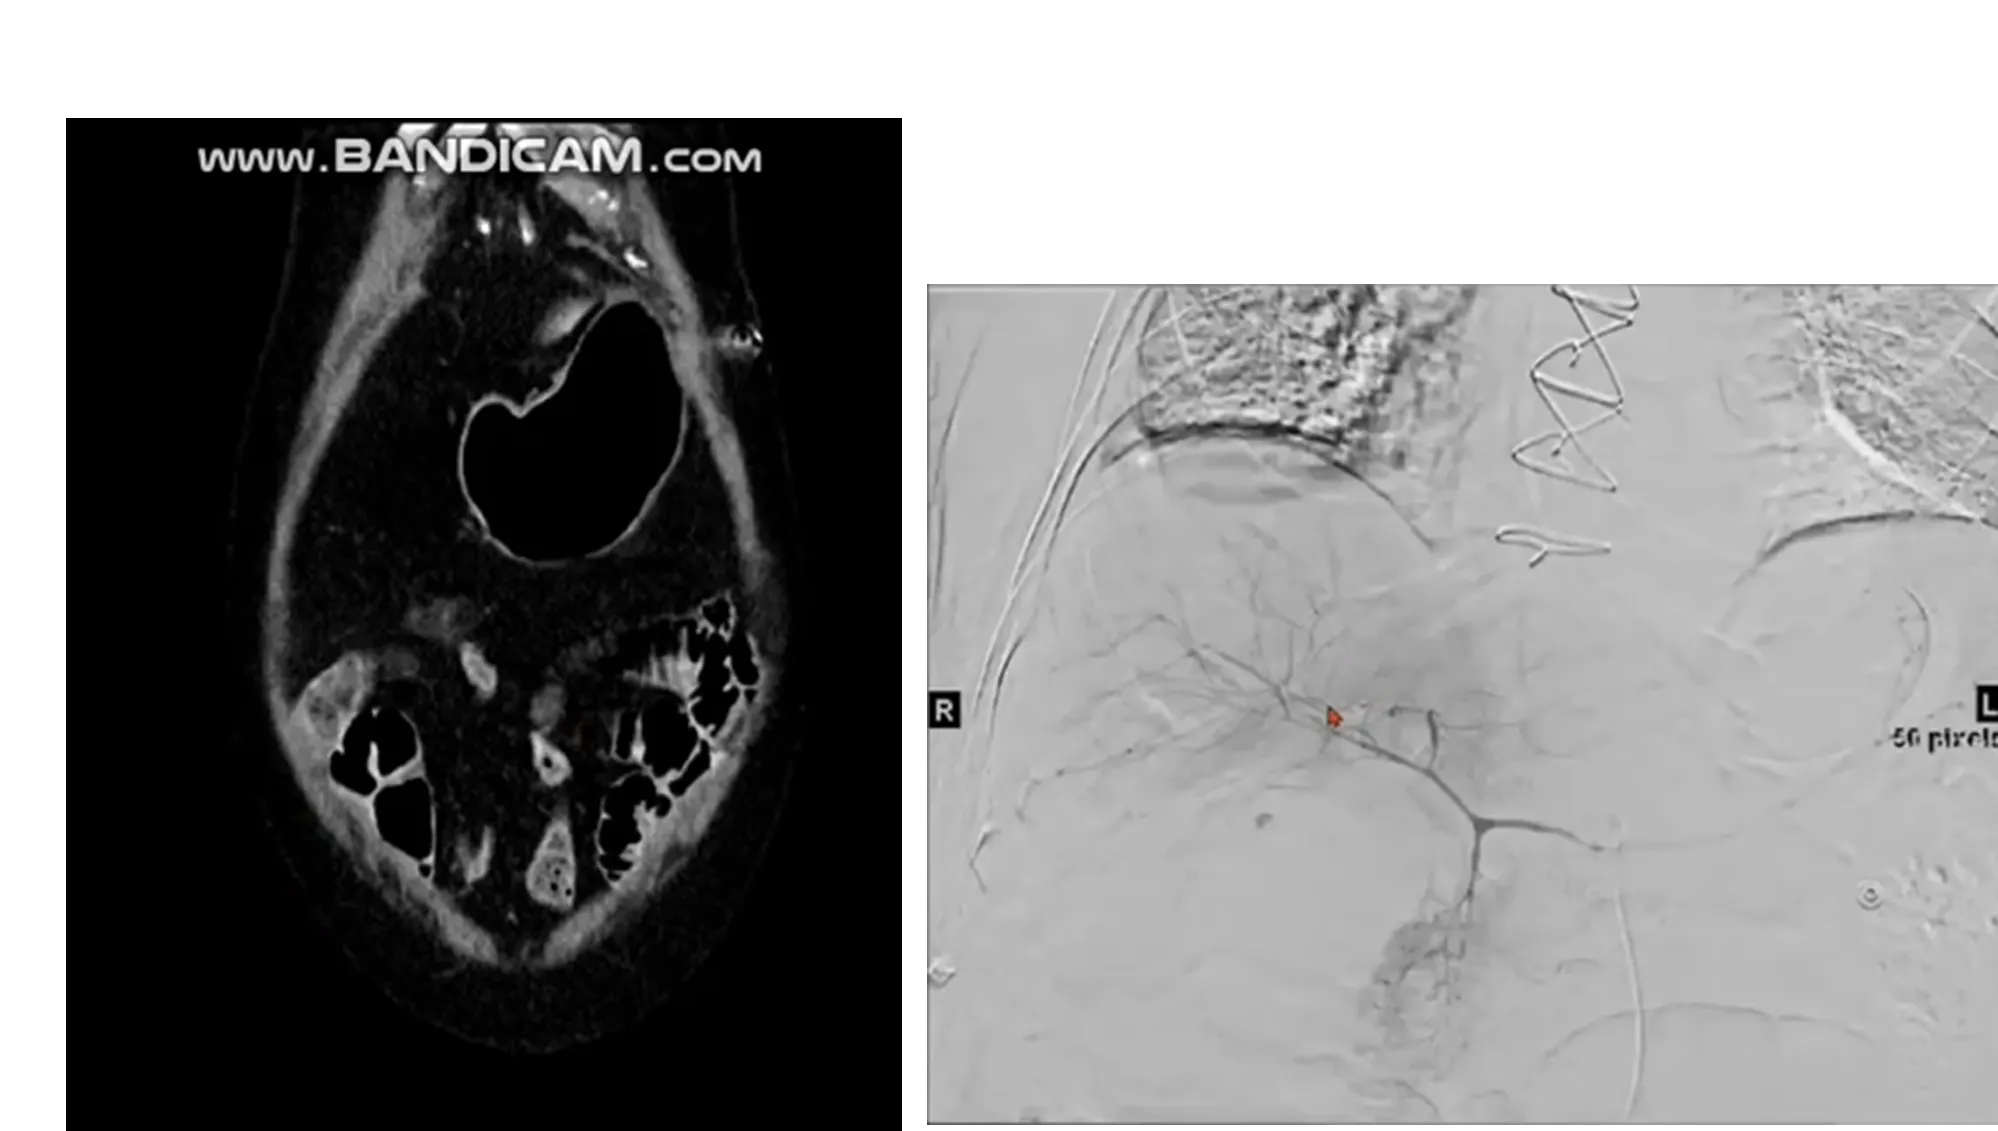

Case 5: Urinary tract infection

•

M/77

C/C: Lt. PCN remove site leakage, no self voiding

Hx : bladder cancer s/p Op with neobladder